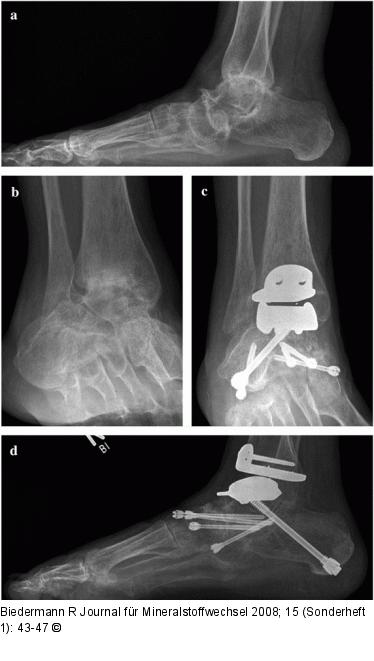

Abbildung 1: Prothese Patientin mit Panarthrose des Rückfußes auf Boden einer primär chronischen Polyarthritis präoperativ (a, b) sowie nach Implantation einer HINTEGRA-Sprunggelenksprothese und simultaner Rückfußarthrodese (c, d) |

Patientin mit Panarthrose des Rückfußes auf Boden einer primär chronischen Polyarthritis präoperativ (a, b) sowie nach Implantation einer HINTEGRA-Sprunggelenksprothese und simultaner Rückfußarthrodese (c, d) |